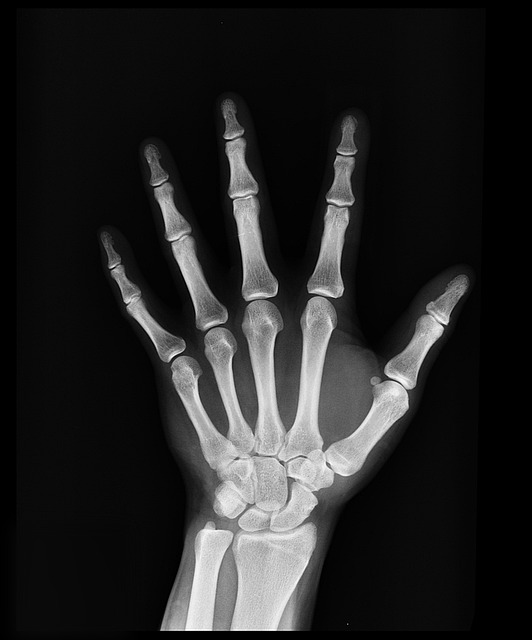

• 혈액 검사 : 류마티스 인자(RF), 항CCP 항체 검사 등을 통해 진단 가능

• 방사선 검사 : 엑스레이, MRI 등을 통해 관절 손상 여부 확인 가능